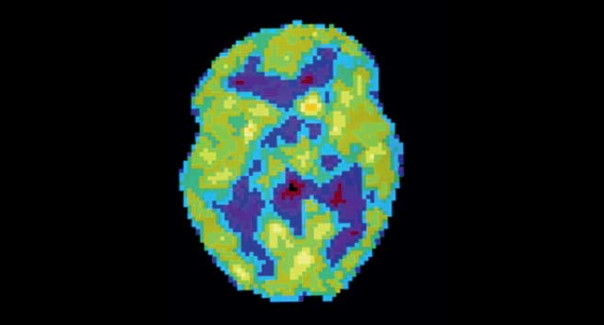

Активность мозга сильно различается не только во время бодрствования и сна — есть множество промежуточных состояний, которые можно различить во время позитронно-эмиссионной томографии.

ДЕПРИВАЦИЯ СНА. Активность мозга очень долго не спавшего человека снижена и похожа на стадию глубокого сна